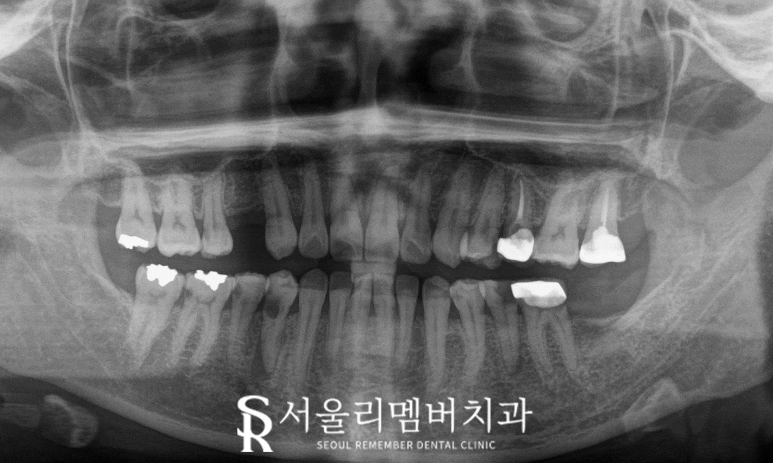

오늘 신림 치과 에서도

결손된 어금니가 있으며,

다발성 우식은 물론이고

보철 아래 이차우식이 생겨

다수의 진료가 필요했던 케이스였는데,

결과적으로 의사의 철학에 따라 기준을 세우고

각 부위마다 적합한 해결을 마쳤습니다.